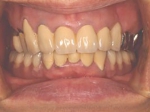

術前口腔内(正面観)

術後口腔内(正面観)もう入れ歯は要らなくなりました。